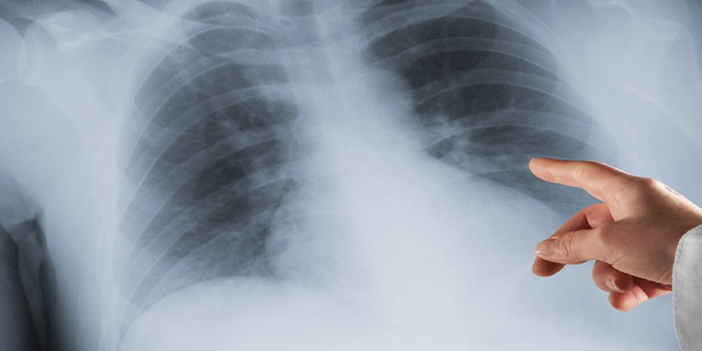

Uzmanlar kadınlarda son dönemde akciğer kanseri vakalarında ciddi artış yaşandığı ve bunun da en büyük nedeninin kadınlarda artan sigara alışkanlığı olduğu belirtildi.

Kadınlarda sigara kullanma alışkanlığının arttığına dikkat çeken Prof. Dr. Celal Tekinbaş, her bölgede olduğu gibi Karadeniz Bölgesinde de akciğer kanseri vakaları daha çok görüldüğünü söyledi. Tekinbaş, “Dünyada kanserden ölümlerin en büyük nedeni, akciğer kanserlerinden kaynaklanıyor. Belli bölgelerde akciğer kanseri daha fazla görülüyor. Bizim bölge de bu bölgelerden bir tanesi. Kanserin en önemli nedeni sigara. Sigara alışkanlığının artmasıyla beraber kadınlarda da artık daha fazla kanser vakalarını görüyoruz. Kanser sayısı oranlarının artmasından çok artık kanserler daha erken teşhis ediliyor. Daha önceden kanser olduğunu bilmediği halde ölen insanlar vardı ama şimdi artık hastalığının ne olduğunu hastanelerin yaygınlaşması tomografi gibi pet gibi biyopsi işlemleri gibi bir çok gelişmeyle insanlar hastalıklarının ne olduğunu biliyorlar. Akciğer kanseri de tanısı artık konulan bir hastalık grubu içerisinde önemli bir yer tutuyor. Daha fazla ameliyat edebildiğimiz hastayla karşılaşıyoruz çünkü daha erken tanı konulabiliyor” dedi.